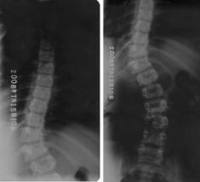

(三)X像檢查

1.直立位全脊柱正側位像。照X相時必須強調直立位,不能臥

脊柱側凸位。若患者不能直立,宜用坐位像,這樣才能反映脊柱側凸的真實清況。是診斷的最基本手段。X像需包括整個脊柱。

2.仰臥位左右彎曲及牽引像。反映其柔軟性。Cobb氏角大於90度或神經肌肉性脊柱側凸,由於無適當的肌肉矯正側凸,常用牽引像檢查其彈性,以估計側彎的矯正度及各柱融合所需的長度。脊柱後凸的柔軟性需攝過伸位側位像。

脊柱側彎x片脊柱側彎目前在我國青少年中的發病率約為1%-3%,這個發病率是相當高的,有0.25%-0.27%需要治療,而真正得到治療的又微乎其微。而我國目前並未將脊柱的檢查納入到學生常規體檢之中,所以學生及家長應格外重視脊柱畸形發生的可能。